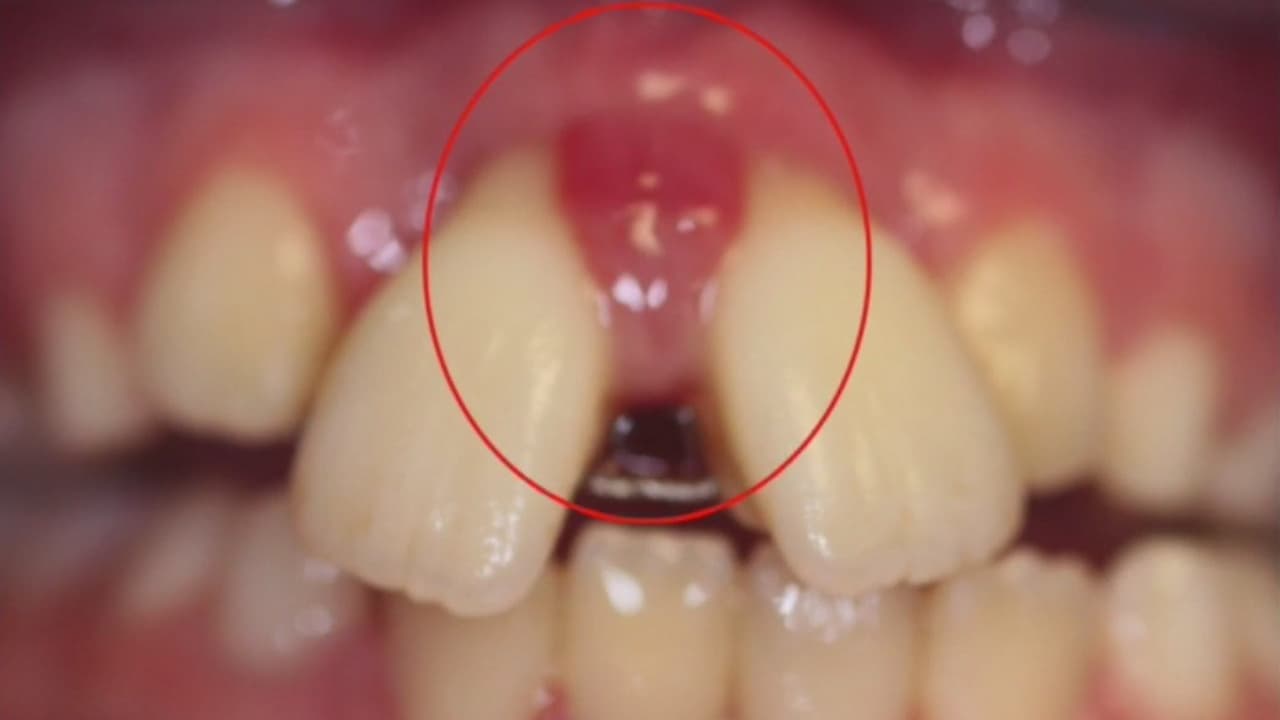

Berenice Gartner, de 41 A Tu Lado, presenta estos casos de jóvenes que se ponen un caucho para cerrar los espacios que hay en los dientes y las terribles consecuencias que esta práctica acarrea.